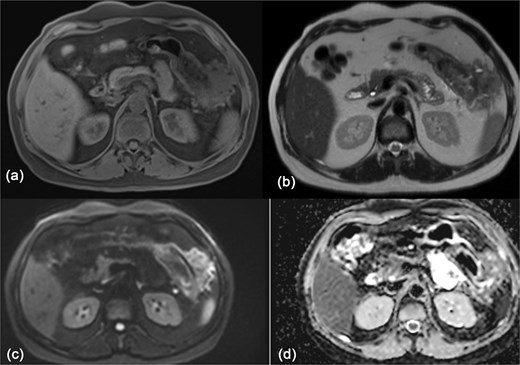

The OGD didn’t show any stomach infiltration or other pathology. CT-guided biopsies were obtained from the mass. Histopathological analysis identified the lesion as a benign fibrous tumor, most consistent with fibromatosis. Further evaluation with magnetic resonance imaging (MRI) showed an exophytic lesion involving the left lateral abdominal wall with invasion into the splenic flexure and lower pole of the spleen (Fig. 3). The patient was then discharged and scheduled for elective surgery.

MRI of the abdomen showing: (a) T1 weighted image showing isointense exophytic mass at the splenic flexure with close proximity to the abdominal wall and inferior pole of the spleen. (b) T2 weighted image showing heterogeneously hypo-to isointense signal. (c, d) Diffusion weighted images with no diffusion restriction within the mass.